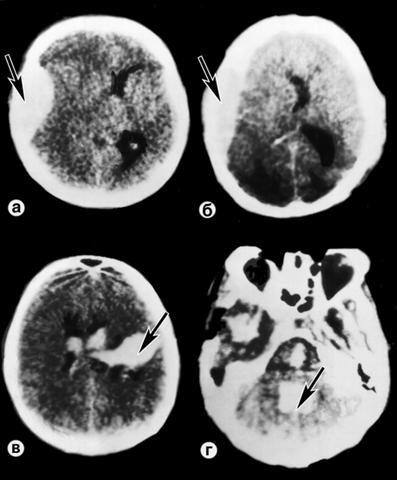

Рис. 2. Компьютерные томограммы при черепно-мозговой травме, сопровождающейся компрессией головного мозга: а — эпидуральная гематома (указана стрелкой); б — субдуральная гематома (указана стрелкой); в — внутримозговая гематома с прорывом в боковые желудочки (указана стрелкой); г — внутрижелудочковая гематома (IV желудочек, указана стрелкой).